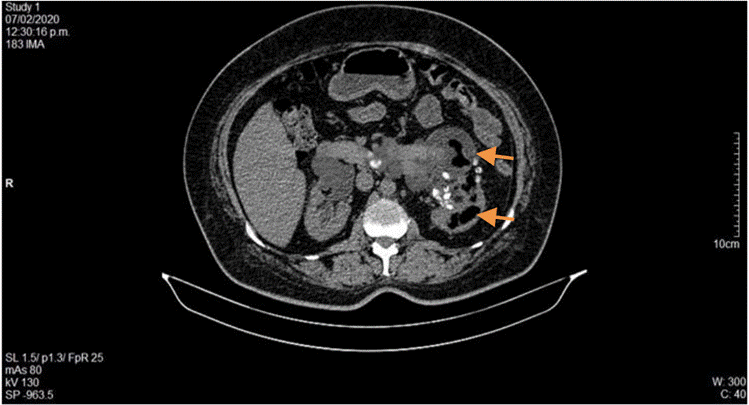

La ecografía abdominal total mostró hallazgos sugestivos de PNE izquierda (Figura 1), por lo que se solicitó valoración por urología; este servicio indicó continuar con la misma terapia antibiótica y realizar UROTAC que mostró microlitiasis renal bilateral, litiasis ureteral izquierda y proceso infeccioso inflamatorio con presencia de gas en el riñón izquierdo, lo que indicó diagnóstico de PNE izquierda tipo 2 (Figuras 2 y 3). Ante los hallazgos radiológicos y el reporte de urocultivo positivo para Escherichia coli multisensible, se decidió hacer rotación de cubrimiento antibiótico a carbapenémicos debido al alto riesgo de mortalidad.

Durante su estancia hospitalaria, el paciente presentó expulsión espontánea de lito, con posterior descenso de azoados desde 2,48 mg/dL de creatinina al ingreso, hasta 1,5 mg/dL, por lo que fue llevado a implante de catéter doble J sin complicaciones. Luego de 21 días de antibiótico, los hallazgos radiológicos (Figura 4) mostraron una disminución de gas en el parénquima renal, por lo cual se le dio el alta hospitalaria y se definió el control para retiro de catéter doble J ambulatoriamente.